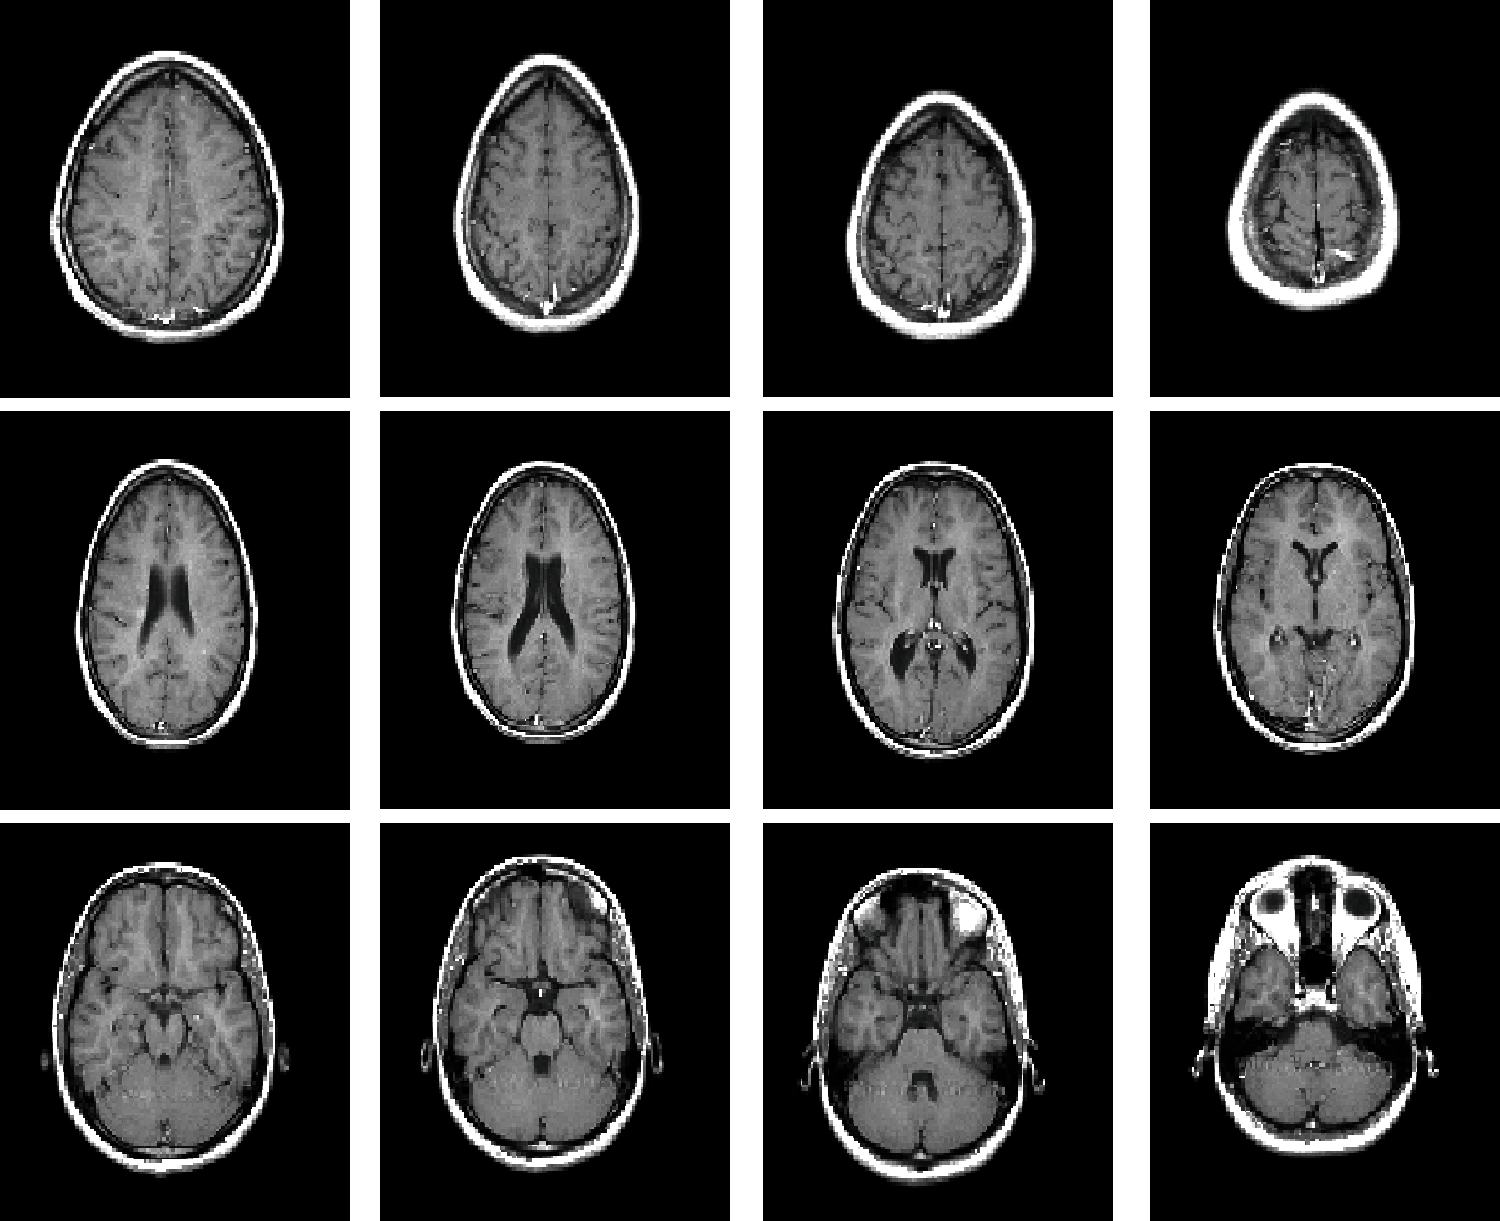

The original 3D model data [27] used for the test is the standard MRI brain data from MATLAB R2019a software. Fig. 4 shows the standard MRI brain slice image, and Fig. 5 shows the MRI brain model and watermark image.

Figure 4: Standard MRI brain slices